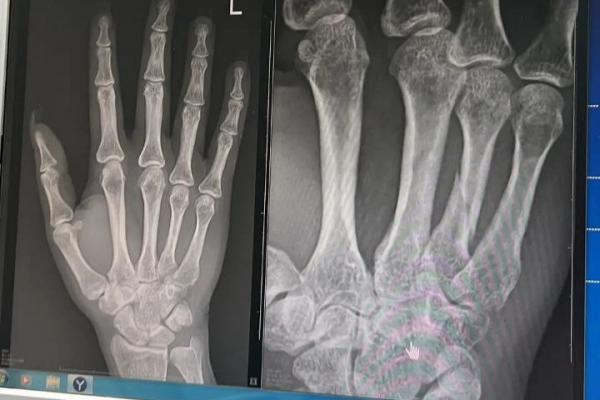

Сделав круг, девушка остановилась на краю трассы, и в ее карт влетел на огромной скорости другой посетитель. От удара транспортное средство отбросило, Ольга больно ударилась о руль. Персонал заведения не оказал пострадавшей первую помощь и не вызвал скорую. Девушка самостоятельно добралась до травмпункта, где у нее диагностировали ушиб мягких тканей головы и грудной клетки, а также перелом диафиза 4-й пястной кости левой кисти со смещением отломков. На руку наложили гипс и сказали ходить в нем не менее пяти недель, после чего понадобится трехмесячная реабилитация.